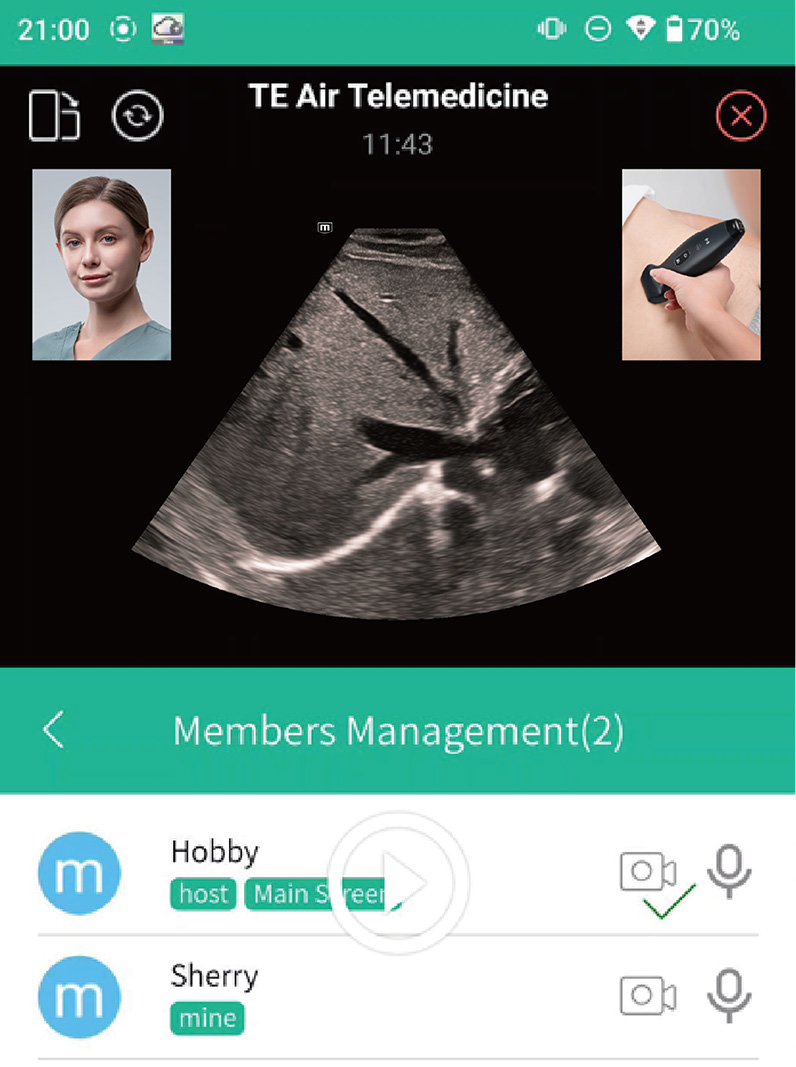

- Ajuda remota: solu??o de colabora??o da Mindray

O TE Air e o Mico+ trabalham juntos realizar o compartilhamento em tempo real de exames de ultrassom, incluindo imagens, ĂĄudio e vĂdeo, para o dispositivo terminal, para orienta??o, treinamento, controle de qualidade, discuss?es de casos e muito mais

Comunica??o em tempo real

Compartilhamento com um clique